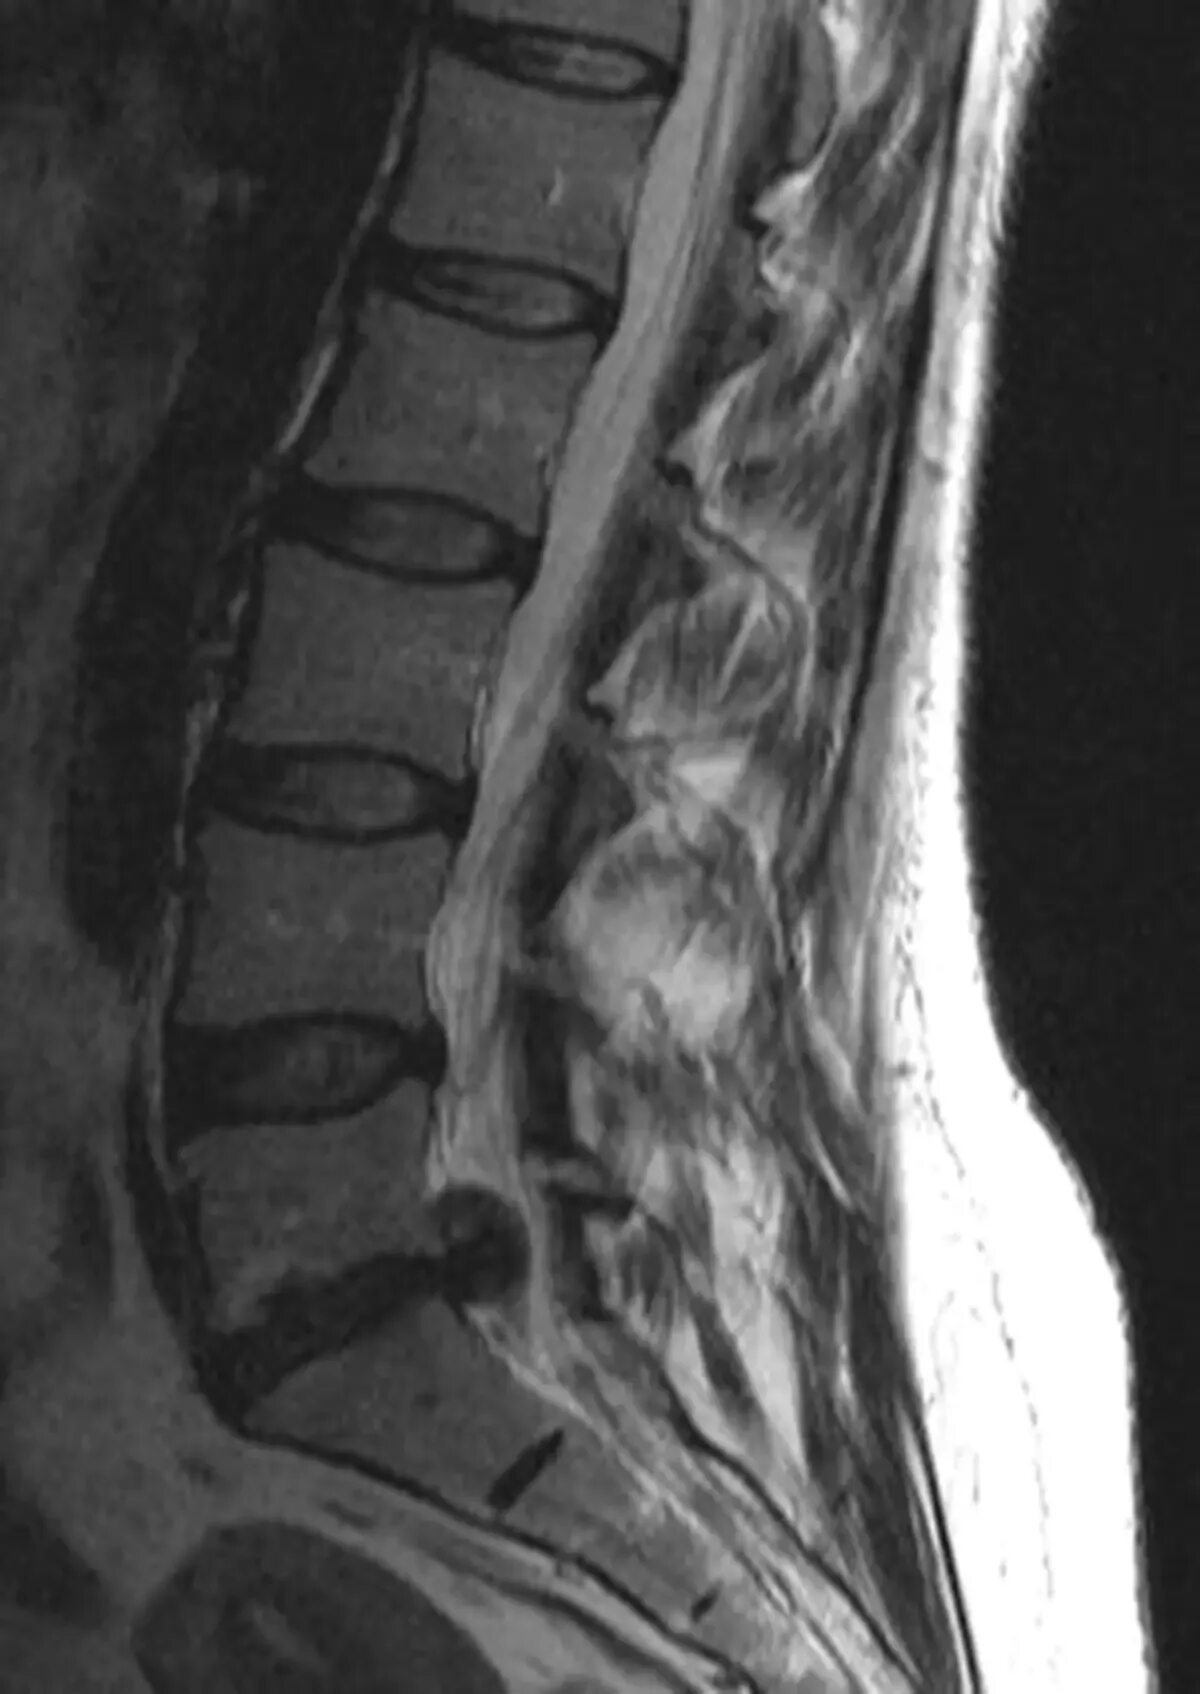

Как выглядит грыжа позвоночника на мрт